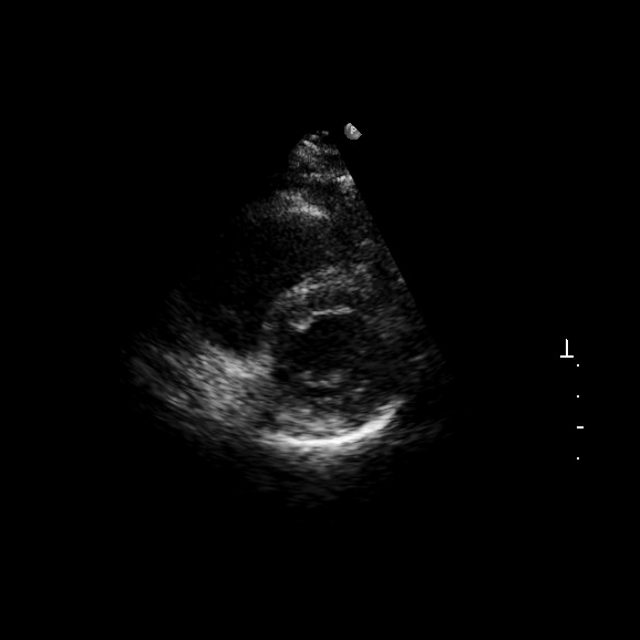

2.3 Interactive Structure Segmentation

We sought to evaluate EchoApex’s effectiveness in structure segmentation, a common yet time-consuming task in echo exams. We use three large public echocardiogram segmentation datasets, CAMUS [Leclerc2019DeepLF], EchoNet-Dynamic (ENDym) [Ouyang2020VideobasedAF], EchoNet-Pediatric (ENPed) [Reddy2023VideoBasedDL], as well as an internal dataset acquired with volume transducers. CAMUS includes left ventricle and left atrium tracings over an entire cardiac cycle. EchoNet-Dynamic provides tracings of the left ventricle in the apical-4-chamber (A4C) view at end-systole and end-diastole. EchoNet-Pediatric offers tracings of the left ventricle in both A4C and parasternal short axis (PSAX) views. The internal dataset comprises tracings of all four chambers, with biplanes utilized for training and evaluation. The number of annotations per dataset is shown in Fig. 4. We used the Dice Similarity Coefficient as our primary evaluation metric, consistent with the public benchmark. Additional details regarding the datasets, experimental setup, and other performance metrics are provided in Methods and Supplementary Table 9.

We build an interactive segmentation model EchoApex-SAM-B (and its variation EchoApex-SAM-S) by incorporating the pretrained EchoApex encoder and prompt-based (including points, box, and text) encoder-decoder modules following SAM [kirillov2023segment], the state-of-the-art foundation model on natural image segmentation. The model architecture is illustrated in Fig. 4. We compare EchoApex-SAM with two types of model. The first is MedSAM [ma2024segment], a foundation model trained on 1.5 million annotated images from diverse modalities, including CT, MRI, X-ray and ultrasound, and it is specialized in general medical image segmentation. The second are sub-task specialist models, e.g. a UNet model [Leclerc2019DeepLF], that are individually trained on and published together with each dataset. Results are illustrated in Fig. 4. We observe that the UNet specialist models generally shows better performance than MedSAM. This hints that adding additional data from different modalities does not necessarily improve the performance of the model on echo segmentation. As echo represents only a small portion (approximately 5%) of the training data in MedSAM, its model performance on echo may be impacted negatively by the imbalanced data distribution. We also observe that EchoApex-SAM-B outperforms both MedSAM and UNet-specialist on all categories in all datasets, achieving an average dice score of 0.927 (95% CI 0.926-0.928), showing an average of 0.23 and 0.57 dice improvement accordingly. This supports the observation that the model pretrained with more in-domain data will boost the performance on the target task.